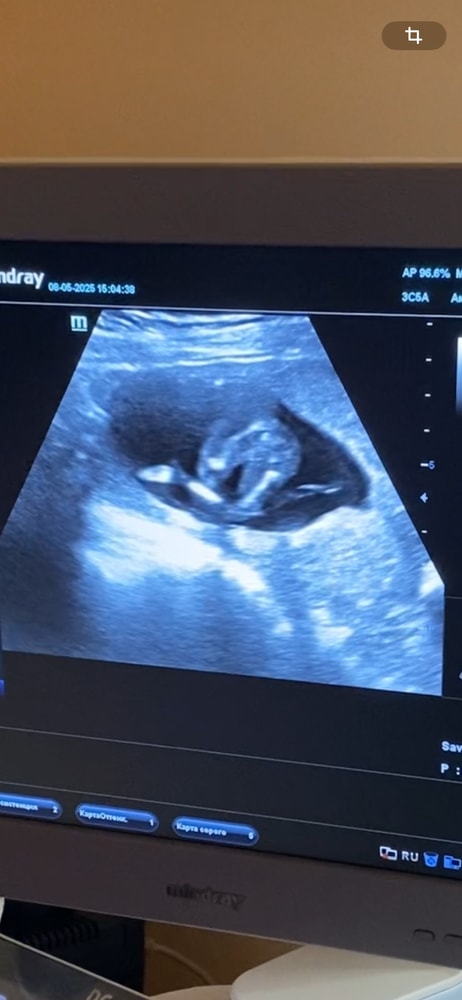

Сегодня срок 39,3 недели. Вчера по узи вес малышки намеряли 3370гр, стоит ГСД, обхожусь без инсулина. Каждый день в голове вопрос «Ну что, может сегодня этот день?» 🤔😁Этот день, когда встречусь со своей малышкой. Лежу в дородовом, сказали до 40,2 не трогают, а после стимулируют. Учитывая это, у меня есть неделька, чтобы роды начались сами 😊